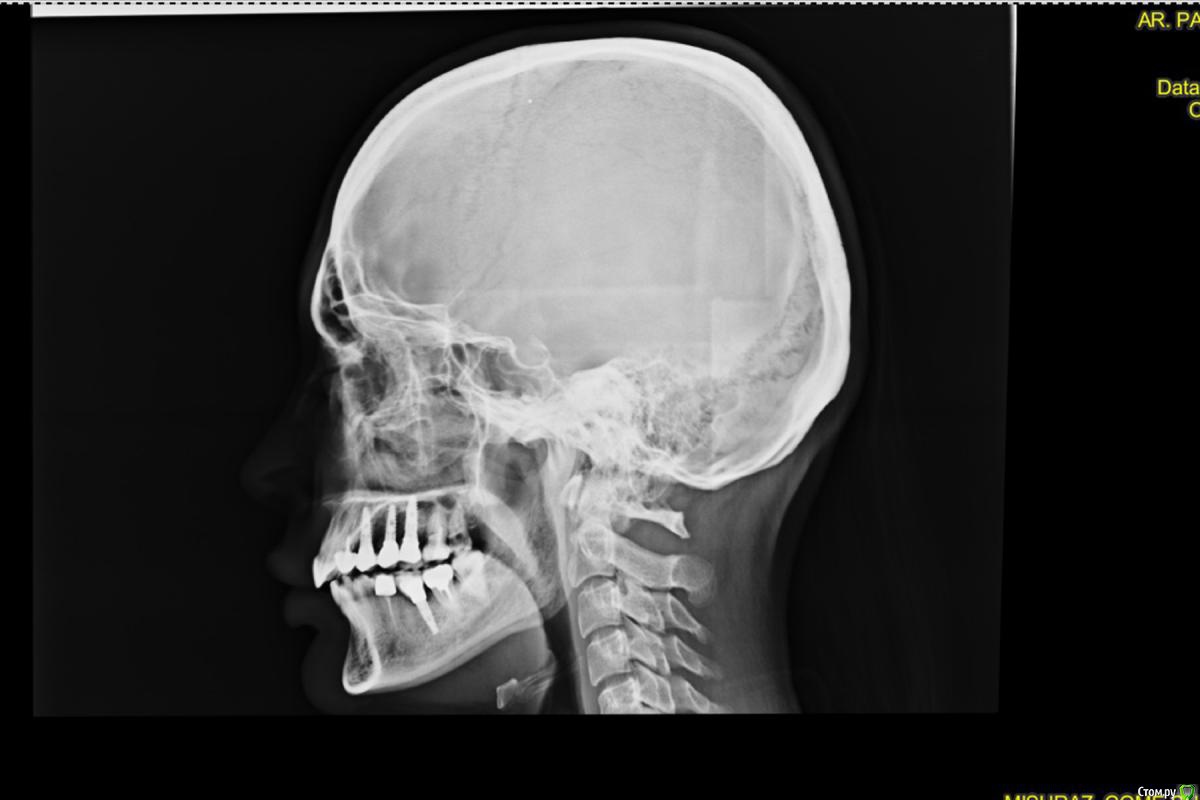

irada Опубликовано 17 декабря, 2019 Поделиться Опубликовано 17 декабря, 2019 Добрый вечер. У меня критическая ситуация. Месяц назад попопала в скорую с температурой и головной болью,выделения из носа не очень обильные но резккий запах, выяснилось -гайморит с левой стороны , сделала курс уколов антибиотиками, но через 2 недели опять поднялась температура и те же самые симптомы , лор отправил делать сникок зубов. У меня как раз с левой стороны подряд 3 импланта сверху , после клыка установлены 3 импланта где жевательные зубы, имланиы были установлены 3 года назад, одновременно с синус лифтингом, врачь говорит что корни имплантов воспалены, вернее кость, там хроническое воспаление, которое вызывает гаймлрит и нужно удалять импланты , чистить, наращивать кость, через время делать новые.Если ли какие то альтернативы? или нет шансов сохранить имплант? Ссылка на комментарий

АнтонТЛТ Опубликовано 17 декабря, 2019 Поделиться Опубликовано 17 декабря, 2019 Лучше сделать компьютерную томографию. Есть подозрение, что проблема исходит от зубов соседствующих с имплантатами. 2 Ссылка на комментарий

irada Опубликовано 21 декабря, 2019 Автор Поделиться Опубликовано 21 декабря, 2019 что-то по этому снимку и кости то вокруг имплантатов не видно, очень плохое качество.Сделайте дентальную компьютерную томографию верхней челюсти, чтобы туда вошли пазухи с соустьями.Но что-то мне подсказывает, что там все на удаление.мне точно пока не могут сказать нужно ли удалять, сказали может придется как то восстанавливать мембрату потому что имлант пробил синус. и что у меня кость гниет. что надо отрезать кусочек корня импланта восттанавливать мембрану. наращивать кость. но при этом не удалять имплант. я просто первый раз о такой операции слышу Ссылка на комментарий

колесников Опубликовано 22 декабря, 2019 Поделиться Опубликовано 22 декабря, 2019 Очень тонкая кость может быть не видна снимке,в том что имплант на снимке выступает в полость пазухи ,ничего криминального нет,итальянские коллеги только так и ставят . То что вам предложили,довольно травматичная операция,необходимо оценить ее целесообразность, Ссылка на комментарий

irada samadova Опубликовано 25 февраля, 2020 Поделиться Опубликовано 25 февраля, 2020 Очень тонкая кость может быть не видна снимке,в том что имплант на снимке выступает в полость пазухи ,ничего криминального нет,итальянские коллеги только так и ставят . То что вам предложили,довольно травматичная операция,необходимо оценить ее целесообразность,Как мне объяснил врач он сказал что имплант который у меня он не предназначен чтоб его ставили в пазуху что для пазухи импланты с более округлым концом Ссылка на комментарий